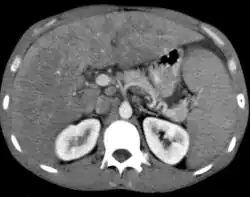

Non-Hodgkin lymphoma - splenic involvement

Non-Hodgkin lymphoma with hepatic involvement